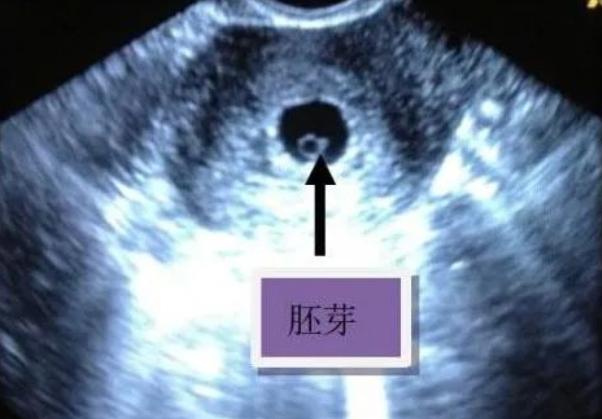

胚胎早期B超往往先看到卵黄囊,这时孕囊还小,还没有发育出胎心胎芽临床上大多规定见卵黄囊后2周之内要见到胎心胎芽,如果见卵黄囊2周以后还没有胎心胎芽,诊断胚胎停育,要给予及时清宫终止妊娠胚胎停育诊断要慎重,不能诊断过早临床上常有胚胎停育诊断过早的情况,比如卵黄囊出现以后没有;特殊人群需更早进行B超检查例如,高龄孕妇有过胎停育史的孕妇等,因胚胎发育风险较高,建议提前进行B超检查,以便及时发现异常并采取干预措施总之,有卵黄囊后胎芽和胎心的出现时间受多种因素影响,需结合个体情况综合判断若有疑问或担忧,应及时咨询医生,并保持良好心态,注意休息和营养,为胚胎。

卵黄囊出现后,胎心胎芽通常在怀孕56周出现,但具体时间因人而异影响胎心胎芽出现时间的因素月经周期若女性月经周期较长,排卵和受孕时间会推迟,导致胎心胎芽出现时间相应延后例如,周期为35天的女性可能比周期28天的女性晚1周左右观察到胎心胎芽受孕时间受孕时间较晚时,胚胎可能尚未发育到;相关事项怀孕早期卵黄囊胎芽和胎心是B超观测孕囊已内的重要结构,这三个结构在怀孕早期是判断孕囊生长发育的重要指标,只有先出现卵黄囊期后才有可能出现胎芽和胎心,进而判断孕囊是否存活正常情况下,一般在怀孕六周左右就应该能看到卵黄囊,出现了卵黄囊以后必须在一定的时间以内出现胎芽和胎心正常情况。

有卵黄囊之后一般一周左右可以看到胎心胎芽,有时胎心胎芽出现较晚,但不会超过两周,如果两周以后仍然未见胎心胎芽,考虑胚胎停育有卵黄囊说明是宫内孕,如果没有卵黄囊不能真正除外宫外孕,有时是宫内的假孕囊,有卵黄囊之后如果迟迟不见胎心胎芽,要考虑胚胎停育的可能但胚胎停育的诊断。